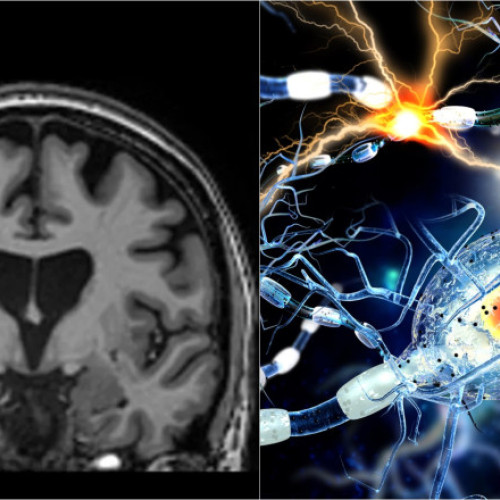

O premieră în tratarea bolii Huntington a fost realizată de compania de biotehnologie UniQure din Amsterdam. Studiul lor a arătat o reducere cu 75% a progresiei bolii la pacienții care au primit un tratament genetic inovator, ce utilizează o tehnică bazată pe micro-ARN. Această boală produce simptome grave, precum spasme involuntare, pierderi de memorie și modificări de personalitate, fiind fatală în cele din urmă. Boala Huntington rezultă dintr-o mutație genetică în